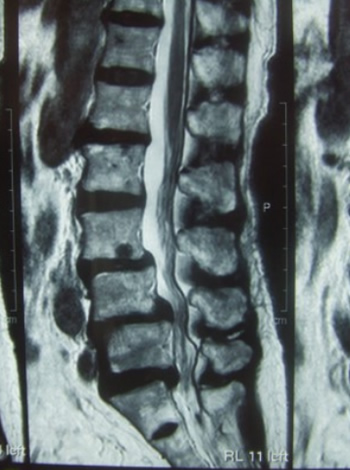

As shown in Fig. 2-1, the lumbar vertebrae have a vertebral foramen, which are connected vertically to form a canal called the spinal canal. The spinal cord is contained in this canal. The spinal cord is then surrounded by the following tissues. In front of the spinal cord, there is an intervertebral disc between the vertebrae, and behind the disc is a longitudinal ligament called the posterior longitudinal ligament. And behind the spinal cord, between the vertebral discs, is the yellow "yellow ligament". The spinal cord is surrounded by the vertebrae, intervertebral discs, posterior longitudinal ligament, and yellow ligament. When these protrude toward the center of the spinal canal due to deformation, herniation injury, or thickening, the spinal canal becomes narrower, putting pressure on the spinal cord causing spinal stenosis.

The mechanism of intermittent claudication is as follows. In scoliosis, the cauda equina nerve, which is located below the second lumbar vertebra. It resembles a horse's tail and is compressed by a deformed yellow ligament or vertebra causing pain and numbness in the lower extremities. The cauda equina nerve has longitudinally distributed blood vessels that supply oxygen and nutrients to the nerve root as shown in Figure 2-2.

As the lumen of the lumbar spinal canal narrows, the nutrient vessels of the caudal nerve are compressed and narrowed. When the lumbar spine kyphosis is strengthened by upper body loading (60% of body weight) during walking, the spinal canal is further narrowed and the pressure on the blood vessels becomes stronger. As a result, blood flow to the cauda equina nerve deteriorates, causing pain and numbness in the lower limbs, making walking difficult (intermittent claudication).

Figure 2-4. Hernia of L3/4 and L4/5 by MRI - Treatment course

Figure 2-6. Anterior slip at L3 and L4, posterior slip at L5, and spinal canal stenosis at L3/4, L4/5, and L5/S1.

Figure 2-7. Compression of the cauda equina nerve from the dorsolateral aspect due to narrowing of the L3.4 intervertebral foramen and thickening of the yellow ligament

Figure 2-8. Stenosis of L3/4, L4/5, and L5/S1 - Treatment course